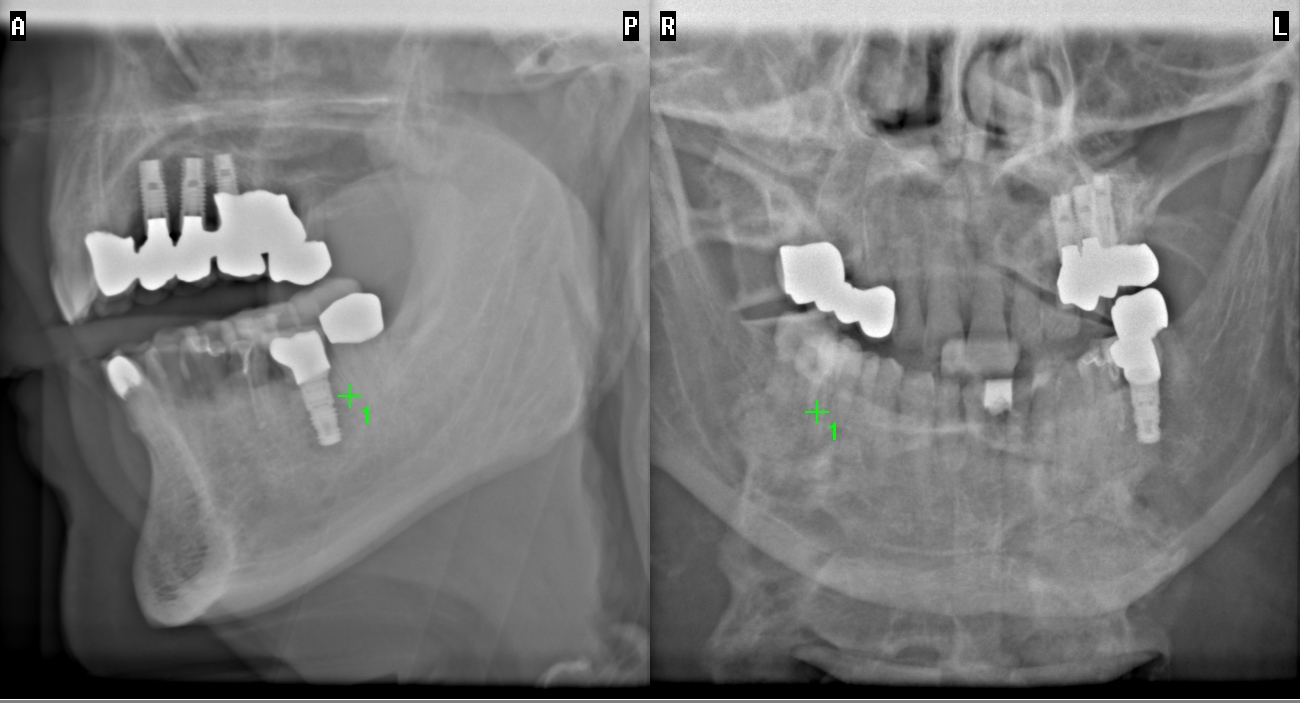

In einem ausführlichen Gespräch klären wir Ihre Wünsche und ob ein Implantat für Sie infrage kommt. Digitale Röntgendiagnostik und 3D-Planung ermöglichen eine präzise Analyse der Knochensituation.

2. Digitale 3D-Implantatplanung

Dank unserer computergestützten Planung mit 3D-Navigation können wir Implantate minimalinvasiv und millimetergenau positionieren – sicher, schonend und vorhersagbar.

Zur Planung der Behandlung müssen Röntgenbilder und ggf. Modelle angefertigt werden. Manchmal ist auch eine dreidimensionale dentale Volumentomographie (DVT) erforderlich, um das vorhandene Knochenangebot genau ausmessen zu können.